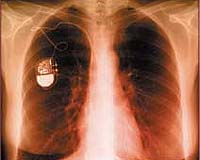

Medical devices such as pacemakers are vulnerable to attacks by hackers, who could gain access to a patient's private details or reprogram their device and put their health in jeopardy, a US study showed Wednesday.

A research team led by computer scientists Kevin Fu of the University of Massachusetts and Tadayoshi Kohno of the University of Washington, and cardiologist William Maisel of Harvard Medical School was able in lab tests to intercept signals sent from an implantable cardiac defibrillator (ICD).